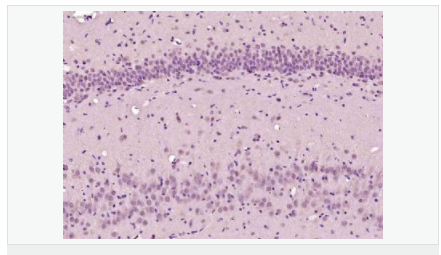

交叉反應(yīng):Mouse,Rat(predicted:Human,Pig,Cow,Horse,Rabbit,Sheep) 推薦應(yīng)用:IHC-P,IHC-F,ICC,IF,ELISA

| 產(chǎn)品應(yīng)用 | ELISA=1:5000-10000 IHC-P=1:100-500 IHC-F=1:100-500 ICC=1:100-500 IF=1:100-500 (石蠟切片需做抗原修復(fù)) not yet tested in other applications. optimal dilutions/concentrations should be determined by the end user. |